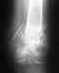

Смещенние позвонка

Последствия травмы Отправлено Анна 16 Март 2010, 14:03

У меня смещение

В верхнем поясничном отделе. Что с этим делать??Куда мне обратиться?